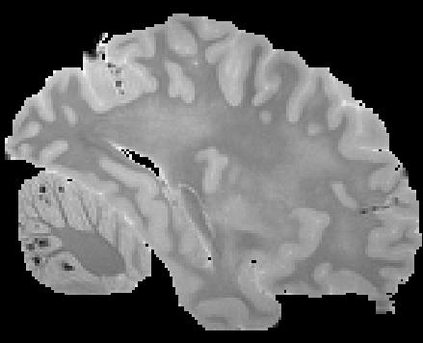

In neuroimaging, MRI tissue properties characterize underlying neurobiology, provide quantitative biomarkers for neurological disease detection and analysis, and can be used to synthesize arbitrary MRI contrasts. Estimating tissue properties from a single scan session using a protocol available on all clinical scanners promises to reduce scan time and cost, enable quantitative analysis in routine clinical scans and provide scan-independent biomarkers of disease. However, existing tissue properties estimation methods - most often $\mathbf{T_1}$ relaxation, $\mathbf{T_2^*}$ relaxation, and proton density ($\mathbf{PD}$) - require data from multiple scan sessions and cannot estimate all properties from a single clinically available MRI protocol such as the multiecho MRI scan. In addition, the widespread use of non-standard acquisition parameters across clinical imaging sites require estimation methods that can generalize across varying scanner parameters. However, existing learning methods are acquisition protocol specific and cannot estimate from heterogenous clinical data from different imaging sites. In this work we propose an unsupervised deep-learning strategy that employs MRI physics to estimate all three tissue properties from a single multiecho MRI scan session, and generalizes across varying acquisition parameters. The proposed strategy optimizes accurate synthesis of new MRI contrasts from estimated latent tissue properties, enabling unsupervised training, we also employ random acquisition parameters during training to achieve acquisition generalization. We provide the first demonstration of estimating all tissue properties from a single multiecho scan session. We demonstrate improved accuracy and generalizability for tissue property estimation and MRI synthesis.